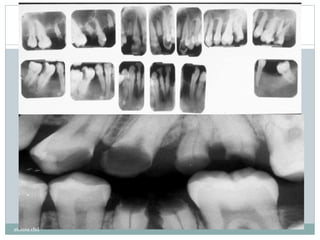

‫ند‬‫و‬‫ر‬‫پوسیدگی‬‫باعث‬‫ن‬‫دمینرالیزاسیو‬‫مینا‬‫وعاج‬‫می‬‫شود‬‫و‬‫ضایعه‬‫پوسیدگی‬‫به‬‫ص‬‫ت‬‫ر‬‫و‬‫ناحیه‬

‫ادیلوسنت‬‫ر‬(‫تیره‬‫تر‬)‫دیده‬‫می‬‫شود‬

‫یرا‬‫ز‬‫ناحیه‬‫دمینرالیزه‬‫شده‬‫دندان‬‫ن‬‫فوتو‬‫های‬‫اشعه‬‫ایکس‬‫ا‬‫ر‬‫به‬‫ه‬‫ز‬‫اندا‬‫ناحیه‬‫تحت‬‫ت‬‫اثیر‬‫قرار‬

‫نگرفته‬‫جذب‬‫نمی‬‫کند‬.

پوسیدگی در رادیوگرافی